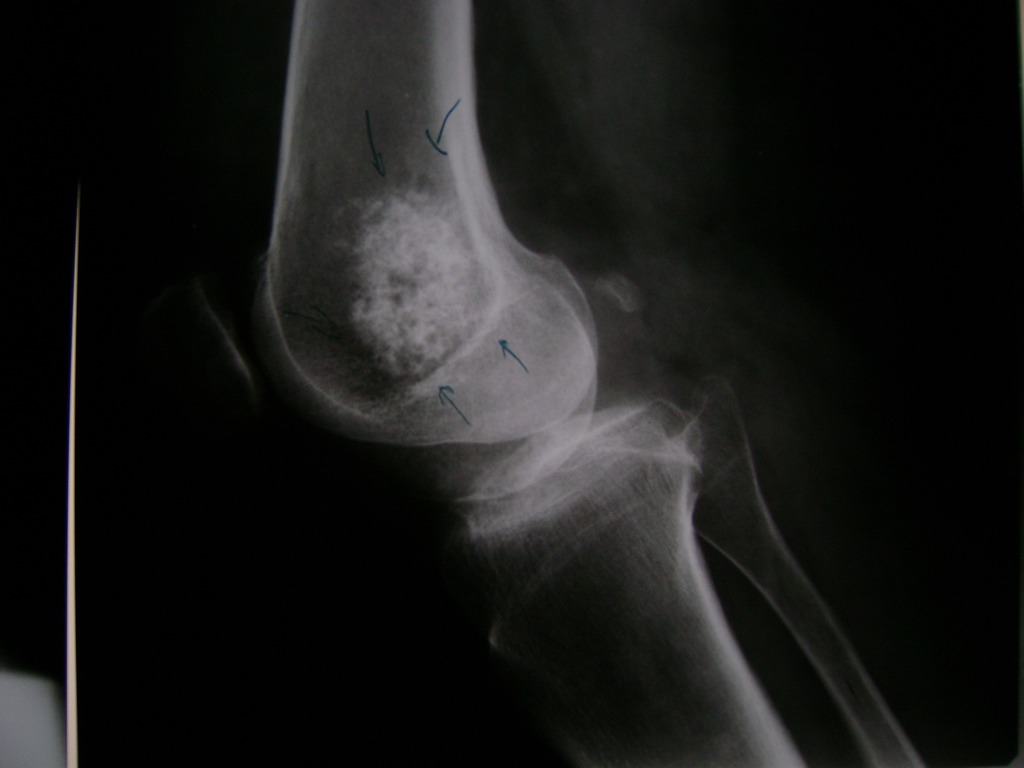

Cirugías de Peroné y Tibia

La artroscopia de rodilla es un cirugía en el cual la estructura interna de la articulación es examinada ya sea para realizar un diagnostico o para realizar un tratamiento, este procedimiento se realiza utilizando un instrumento parecido a un pequeño tubo llamado artroscopio.